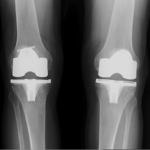

The surgery is performed under spinal or general anesthesia. Your surgeon will make an incision in the skin over the affected knee to expose the knee joint. Then the damaged portions of the femur bone are cut at appropriate angles using specialized jigs. The femoral component is attached to the end of the femur with or without bone cement. The surgeon then cuts or shaves the damaged area of the tibia (shinbone) and the cartilage. This removes the deformed part of the bone and any bony growths, as well as creates a smooth surface on which the implants can be attached. Next, the tibial component is secured to the end of the bone with bone cement or screws. Your surgeon will place a plastic piece called an articular surface between the implants to provide a smooth gliding surface for movement. This plastic insert will support the body’s weight and allow the femur to move over the tibia, similar to the original meniscus cartilage. The femur and the tibia with the new components are then put together to form the new knee joint. To make sure the patella (knee cap) glides smoothly over the new artificial knee, its rear surface is also prepared to receive a plastic component. With all the new components in place, the knee joint is tested through its range of motion. The entire joint is then irrigated and cleaned with a sterile solution. The incision is carefully closed, drains are inserted and a sterile dressing is placed over the incision.